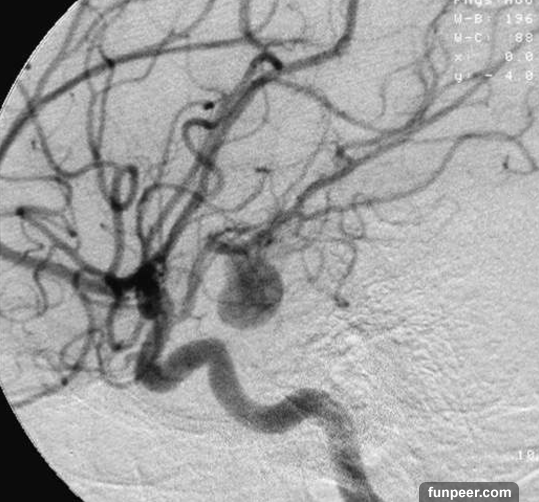

醫生檢查後發現,小李患上了腦動脈瘤。然而,這種病其實很常見,不管男女老少,有沒有家族病史,大家都可能罹患這種病,算是常見的腫瘤。小李的動脈瘤,讓她的血管像氣球一樣膨脹,壓迫到動脈瘤周圍的腦組織,讓她頭痛!

可是小李卻永遠無法回來了,再也無法抱抱8歲的小兒子!醫生說「腦動脈瘤」造成的血管擴張,其實不一定致命!如果動脈瘤急劇膨脹,甚至爆裂的時候,病人的生命就危險了!

「腦動脈瘤」會讓你頭痛,醫生強調:「這一種頭痛,千萬不可以忽視!」得到動脈瘤的人都說:「就像被雷打到一樣,讓人站都站不起來!」